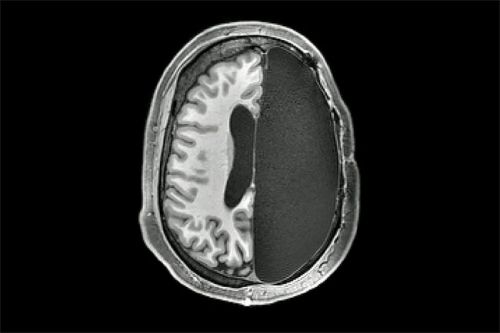

Bộ não hoạt động thế nào nếu bị cắt bỏ một nửa?

Thứ Sáu, 29/11/2019Phẫu thuật cắt bán cầu não được thực hiện tốt nhất với bệnh nhân ở độ tuổi rất nhỏ, trước khi lên 4 hoặc 5. Trẻ em có thể lấy lại chức năng bình thường khi lớn lên.